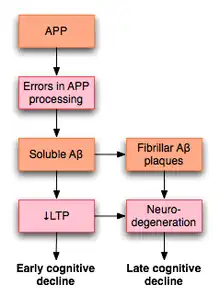

- Delirium and dementia such as Alzheimer's disease